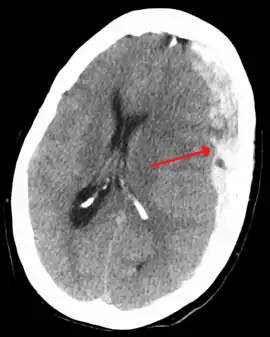

| Subdural hematoma as marked by the arrow with significant midline shift | |